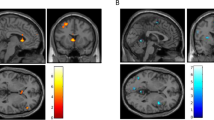

The resting-state seed-based correlation analysis revealed a significant group effect in connectivity at follow-up for bilateral posterior insula (PI) seeds (Fig. 3, N = 18 rTMS, N = 21 sham, per-voxel P < 0.002, cluster corrected at α = 0.05). Both groups revealed a positive correlation between right PI and left precuneus; however, the correlation was significantly lower in the rTMS group [Fig. 3b, rTMS < sham, MNI = 1, −23, 31, cluster size = 8, F(1,36) = 22.88, P < 0.001 η2p = 0.4]. Correlation between left PI and right cingulate was significantly different between groups with positive correlations scores in the rTMS group and negative for the sham group [N = 18 rTMS > N = 20 sham, MNI −11, −71, 28, cluster size 8, F(1, 36) = 15.88, P < 0.001, η2p = 0.3] (Fig. 3b). β Correlation coefficients scores in the rTMS treatment group were not affected by insular depth (Ps > 0.1).

Resting-state connectivity analysis at follow-up. a Insula seed locations identified by maximizing the bilateral connectivity of each seed location. b Brain regions showing significantly different correlation scores in rTMS and sham groups between right PI seed regions and left precuneus and left PI seed and right posterior cingulate (per-voxel P < 0.002, cluster corrected at α = 0.05). The rTMS group presented a significantly lower connectivity between left PI and left precuneus [rTMS < sham, MNI = 1, −23, 31, cluster size = 8, F(1, 36) = 22.88, P < 0.001 η2p = 0.384] and a significantly greater connectivity between left PI and right cingulate [N = 18 rTMS > N = 20 sham, MNI −11, −71, 28, cluster size 8, F(1, 36) = 15.88, P < 0.001 η2p = 0.3]